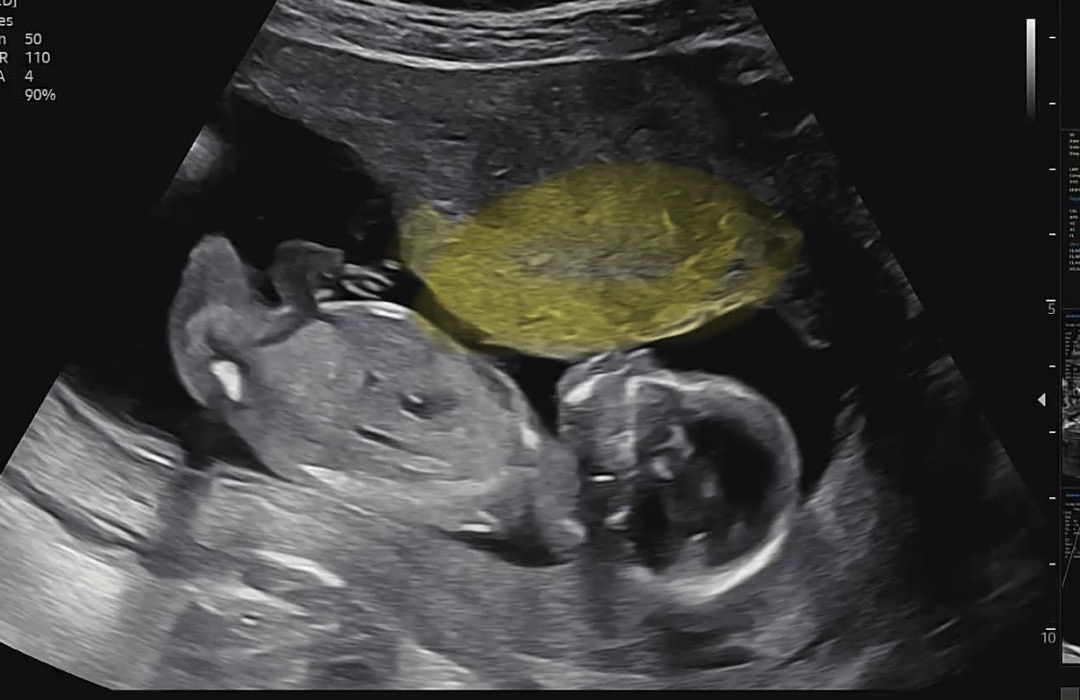

14주 성별보느라 의사선상님께 못여쭤봤네요 ㅠ 애기가 좀 좁아보이규 얼굴을 누르는것같은 위에 노란부분 표시드린건 뭘까요????

저게 태반이지 않나요?

자궁이요~ 초음파 찍는 모습에 따라서 계속 바껴요